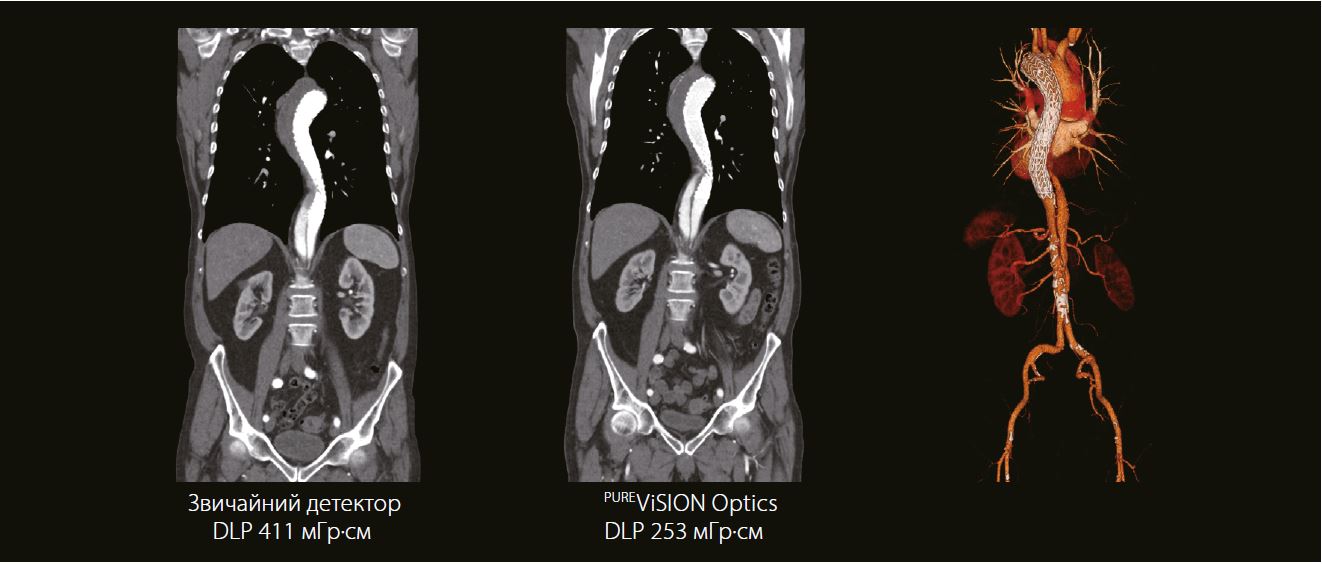

77-річний чоловік звернувся до рентгенологічного відділення на контрольне обстеження після встановлення стента аорти з приводу розшарування типу В. Для виключення ускладнень після хірургічного втручання було призначено КТА дослідження аорти.

Розшарування типу B видно під час контрольного сканування, проведеного через 2 роки після лікування. Контраст візуалізується в помилковому просвіті грудної аорти без розширення, що вказує на стабільність процесу. Сканування, виконане за допомогою PUREViSION Optics, є більш чітким, має менше артефактів і знижує дозу випромінювання.

Звичайний детектор

CTDI: 5.5 мГр

DLP: 402.3 мГр∙cм

Ефективна доза: 5.83 мЗв

PUREViSION Optics

CTDI: 3.5 мГр

DLP: 249.2 мГр∙см

Ефективна доза: 3.61 мЗв